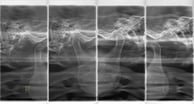

矯正など骨格的な診断が必要な場合はセファロX線写真

その他にも顎関節を撮るレントゲンなど、必要に応じていろんな形でX線写真を撮ります。